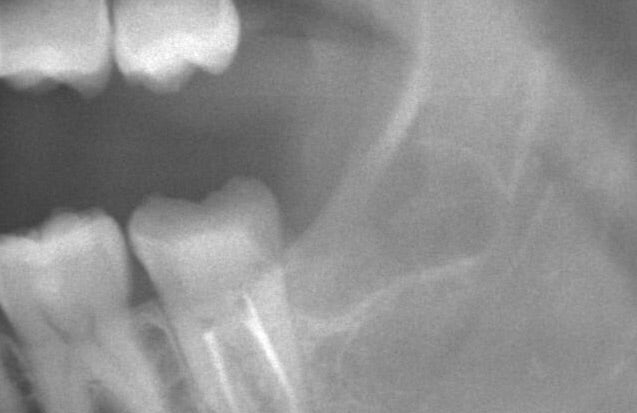

上の写真の様に親知らずが横向きに生えてしまい、他院で抜歯が出来ないと言われ、当院にいらっしゃる患者様が沢山いらっしゃっています。(ご自身で検索される方、他院よりご紹介いただく方等)

横向きの親知らずを抜歯する際には、通常歯茎の切開や、骨の削除、歯の分割を必要とするため、

このケースでは親知らずの根の先が神経と接触している状態でしたが、抜歯までの施術時間は約30分で終了しました。